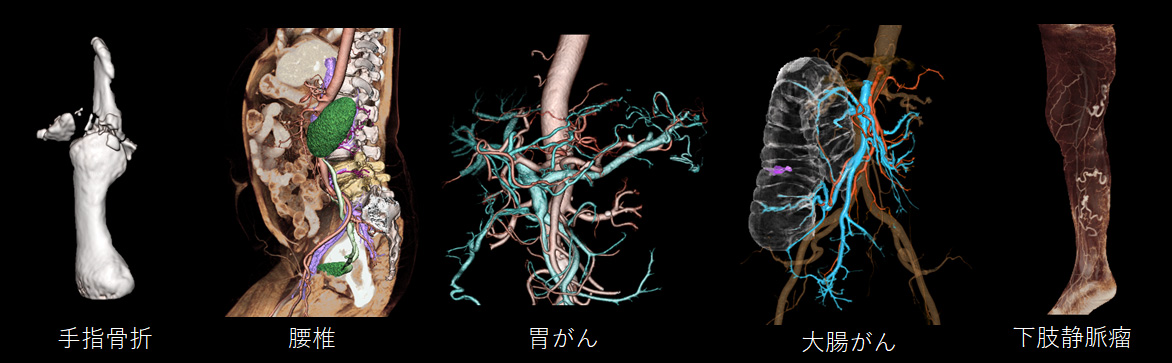

3D画像 を用いた手術シミュレーションにより安全な手術を提供

CT検査で撮影した画像を最大限有効活用して、診断用・治療用・患者様説明用に3D画像を作成しています。3D画像は、CT画像と比べて多彩かつ立体感があるため、誰が見ても病態を理解しやすい特徴があります。また医療従事者にとっても手術のシミュレーションをする際に欠くことのできない存在です。

これらの精細な画像を機械的に作成することは困難であり、非常に多くの知識と高度な技術が必要となります。当院では人の手による高精細かつ丁寧な画像提供を行っています。